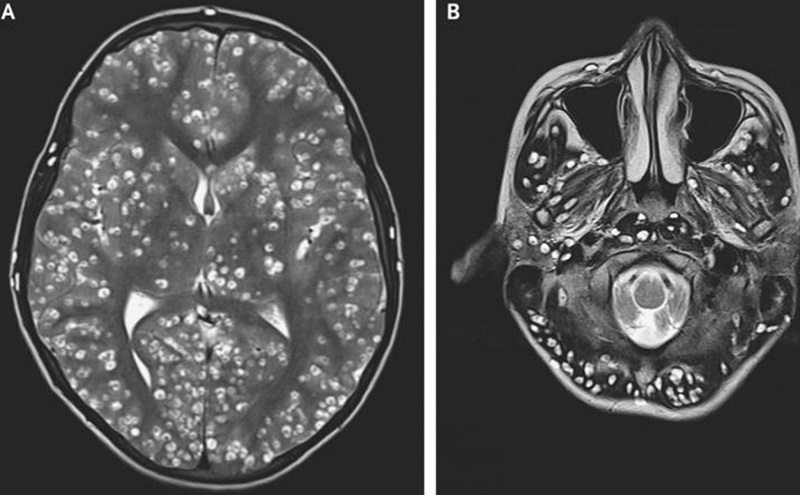

3.2. MRI (Chụp cộng hưởng từ)

Giá trị chẩn đoán

– Phát hiện nang sán ở nhiều giai đoạn khác nhau: hoạt động, thoái hóa, vôi hóa.

– Hiển thị rõ tổn thương ở vị trí sâu như não thất, não giữa, tiểu não.

– Giúp phân biệt sán não với các bệnh lý khác như u não, viêm não, áp-xe…

Ưu điểm

– Hình ảnh chi tiết, chính xác hơn CT.

– Không dùng tia X, an toàn hơn cho bệnh nhân.